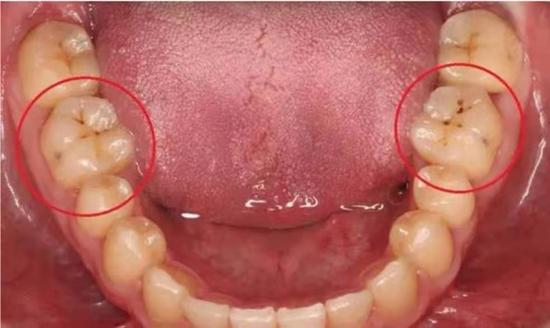

另一种则是牙齿出现了或深或浅的龋坏,从外面看就表现为一个黑点,通常位于窝沟。我们如果多留心自己的牙齿,完全可以把龋坏扼杀在萌芽阶段。如何才能及时发现这种隐匿的蛀牙呢?建议每半年到正规医院进行一次口腔检查。